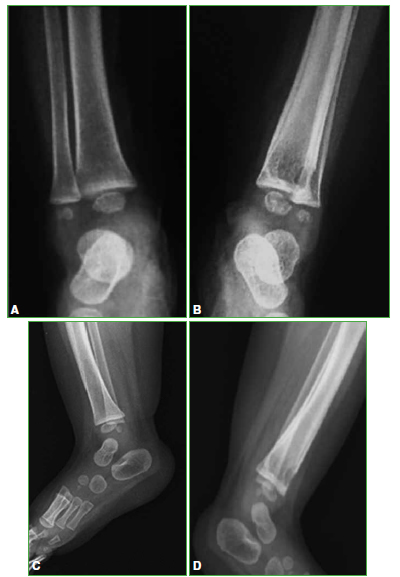

Osteomielitis de tibia secundaria a la vacuna BCG en un paciente pediátrico inmunocompetente. Reporte de un caso

Conclusiones: El compromiso óseo secundario a la vacuna BCG en pacientes previamente sanos es muy raro. Es importante sospecharlo, para diagnosticarlo y administrar el tratamiento adecuado. Se obtuvieron buenos resultados administrando fármacos antituberculosos, sin necesidad de limpieza quirúrgica.